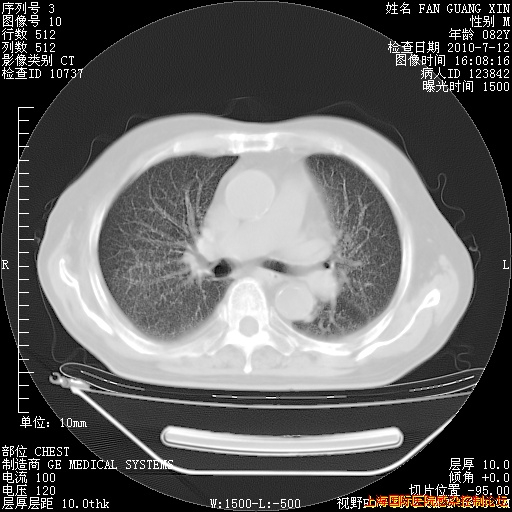

6月12日肺窗

补发6月12日肺部CT肺窗